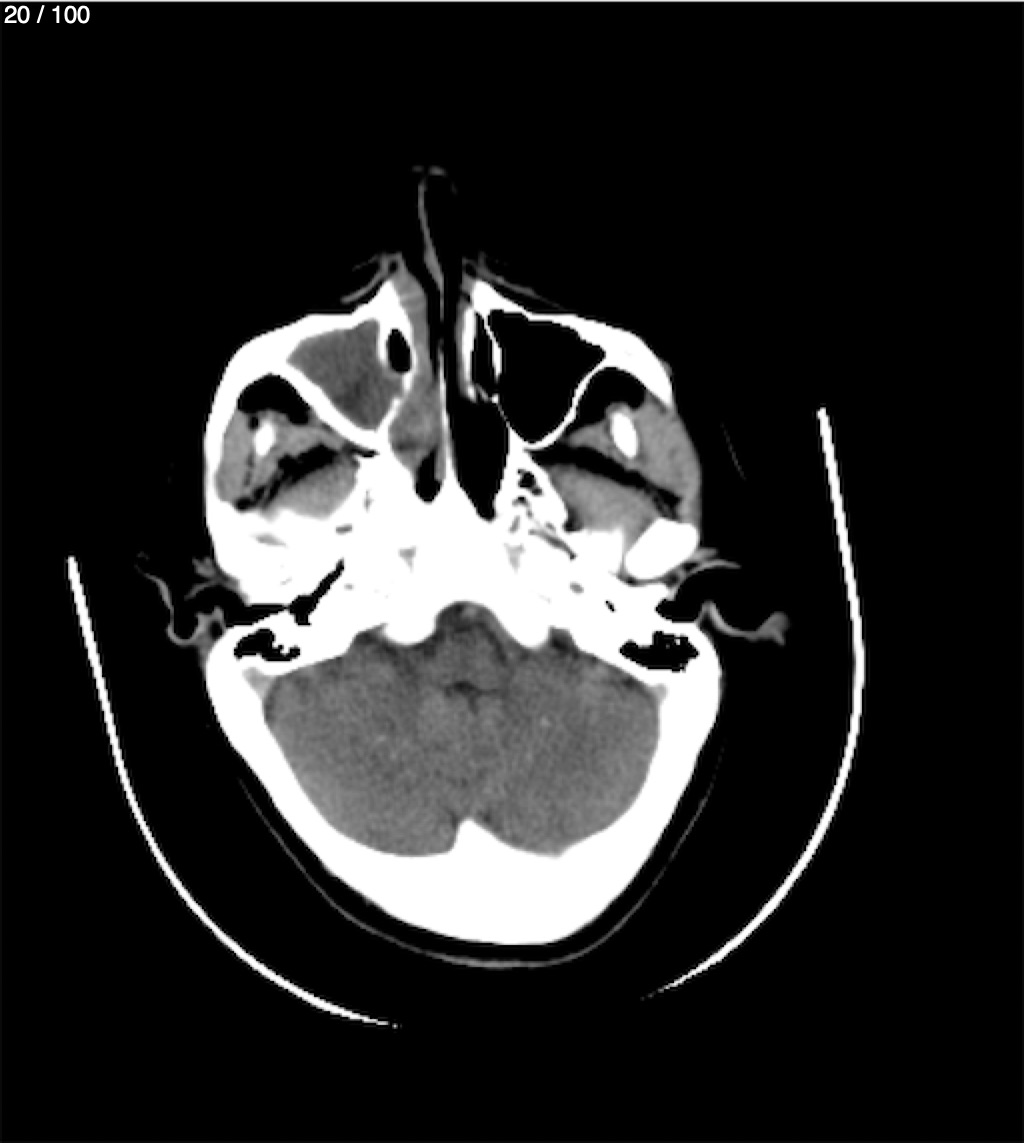

Valentin Perez Gomez 69A - T.C Craneo